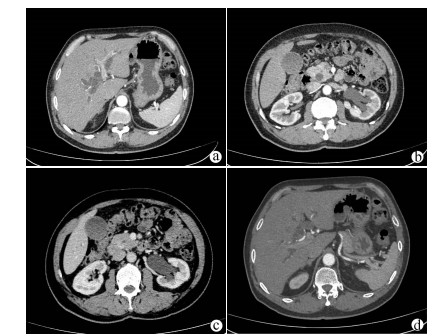

Clinical features, diagnosis, and treatment of IgG4-associated sclerosing cholangitis

Li LI, Hui LIU, Wenyan SONG

2021, 37(8): 1883-1887. DOI: 10.3969/j.issn.1001-5256.2021.08.026

Abstract(1332) HTML (583) PDF (2114KB)(94)

Abstract:

Objective  To investigate the clinical features, diagnosis, and treatment of IgG4-associated sclerosing cholangitis (IgG4-SC).  Methods  A retrospective analysis was performed for the clinical data of 25 patients who were diagnosed with IgG4-SC in Beijing YouAn Hospital, Capital Medical University, from January 2014 to September 2020, and an electronic medical record system was used to collect general information, medical history, diagnosis and treatment processes, laboratory examination, imaging data, and pathological data. Clinical features, process of confirmed diagnosis, and cause of misdiagnosis were analyzed. Normally distributed continuous data were expressed as mean±SD, and the non-normally distributed continuous data were expressed as M(Pminimum value-Pmaximum value).  Results  Among the 25 patients with IgG4-SC, there were 21 (84%) male patients, and the mean age was 57.61±9.73 years. Common initial symptoms included jaundice and/or yellow urine in 18 patients (78.26%) and weakness in 9 patients (39.13%). As for imaging classification, 16 patients (64%) had type Ⅰ IgG4-SC, no patient had type Ⅱa IgG4-SC, 4 (16%) had IIb IgG4-SC, 1 (4%) had type Ⅲ IgG4-SC, and 4 (16%) had type Ⅳ IgG4-SC. Pancreatic involvement was observed in 22 patients (88%). Glucocorticoids were the main treatment method, and total bilirubin achieved a mean reduction of 67.48% within 2 weeks. Among the 22 patients with a confirmed diagnosis in our hospital, 15 (68.18%) were suspected of "space-occupying lesions in the pancreatic and biliary system" and 5 (22.73%) were suspected of obstructive jaundice at the outpatient service. Understanding of IgG4-SC was achieved by postoperative pathology in the early stage, then imaging doctors gradually became aware of this disease, and finally multidisciplinary consultation made more physicians understand the disease, which helped to make a confirmed diagnosis earlier.  Conclusion  For patients with obstructive jaundice, clinical physicians need to identify IgG4-SC based on clinical manifestations and especially imaging features. Multidisciplinary consultation involving imaging and pathology plays an important role in helping clinicians understand this disease and making a confirmed diagnosis.